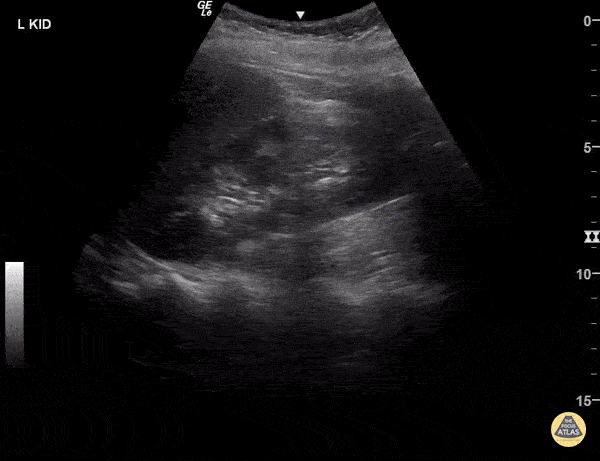

https://www.thepocusatlas.com/renal